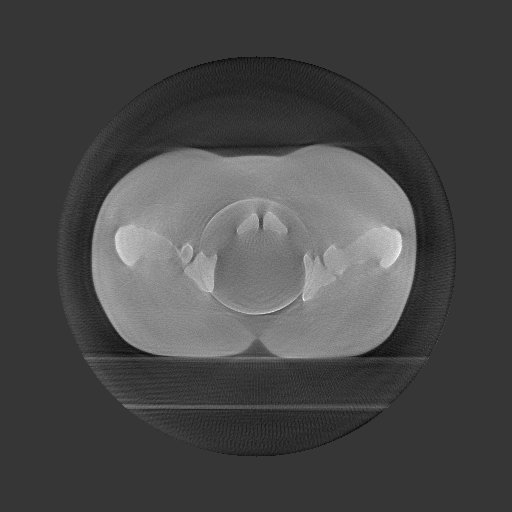

I am now working on iterative reconstruction  offset detector CBCT

using my elekta data.

However, probably because the data is truncated , the ring artifact

appears in the iterative reconstruction.

One of the reasons was that flat field correction was not performed.

[image: recon.jpg]

Name: recon.jpg